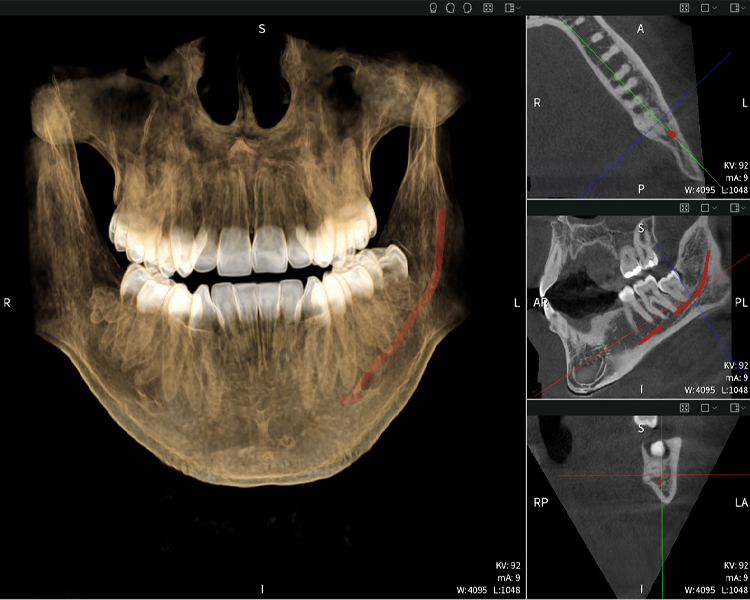

Below you will find a case from Dr. med. dent. Oliver A. Centrella, in which the CBCT images obtained with Seethrough Max provided crucial information on the complex anatomy and the critical relationship between the wisdom teeth and the inferior alveolar nerve. In this case, there is a indication for the surgical removal of the wisdom teeth.

Figure a

- Top left: Axial cross-section of the left mandible (region 38) showing the inferior alveolar nerve (red) in proximity to the roots of tooth 38.

- Top right: 3D reconstruction of the entire mandible for orientation. The red-marked inferior alveolar nerve illustrates its location within the jawbone.

- Bottom left: Sagittal view of the mandible (region 38), highlighting the close spatial relationship between the roots and the nerve canal.

- Bottom right: Coronal view of the mandible (region 38), which is crucial for assessing the spatial position of the roots relative to the nerve.